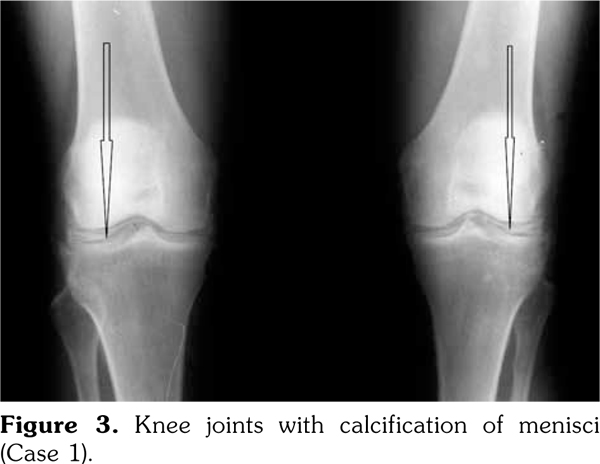

On examination, there was swelling and painful restriction of movement in her right knee. Imaging revealed calcification of cartilage of wrists, knee joints and hip joints although no microscopic confirmation was possible at this stage (Figure 1-4). She was investigated for a possible cause for CC, although investigations to screen for a metabolic cause turned out to be negative with a possibility for hereditary CC.

Case 1- A 35-year-old female patient was admitted to the hospital with an episode of community acquired pneumonia. During her stay at the hospital, she developed a right knee joint pain and an effusion. Joint sepsis was excluded by an orthopedic surgeon. However, during her stay, she complained of pain in both knees and wrist joints needing a rheumatology consultation.

She gave a history of recurrent pain and swelling of her right knee joint and wrists for the past five years and was treated symptomatically by a general practitioner. These episodes were self- limiting and resolved usually within two to three weeks. There was a family history of her father and younger sister having similar problems and her father (64 years old) was being followed-up at the clinic for CC. A written informed consent was obtained from the patient.